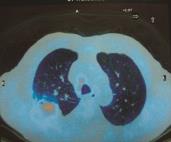

入院后积极完善相关检查:血常规:WBC 10.26×109/L,RBC 4.72×1012/L,Hb 131g,N 85.3%,L 8%,M 6.5%,PLT 199×109/L。血沉61mm/h,降钙素原>0.5,予以头孢哌酮-舒巴坦钠联合莫西沙星抗炎治疗,2次痰培养阴性,3次痰找TB未见,治疗第3日体温渐下降,波动在36.8~37.8℃,治疗第7日体温降至正常,10日后复查肺部CT(图1):①右肺上叶及下叶背段多发片状致密影;②右肺上叶后段支气管闭塞,恶性病变不除外,建议患者行气管镜或PET-CT检查。抗炎治疗2周,体温持续正常1周后停用抗生素。PET-CT(图2)示右肺中央型肺癌多发淋巴结转移。纤维支气管镜活检(图3)示右肺上叶非小细胞肺癌,提示鳞癌。右肺上叶刷片和灌洗(图4)查见癌细胞。免疫组化(图5):AE1/AE3(+)CK20(-)CK5/6(+)CK7(-)Ki-67(+)20% P63(+)TTF-1(-)。患者诊断明确,转于笔者医院放疗科行放射治疗。

图1 肺部CT:①右肺上叶及下叶背段多发片状致密影;②右肺上叶后段支气管闭塞,恶性病变不除外

图1 肺部CT:①右肺上叶及下叶背段多发片状致密影;②右肺上叶后段支气管闭塞,恶性病变不除外(续)